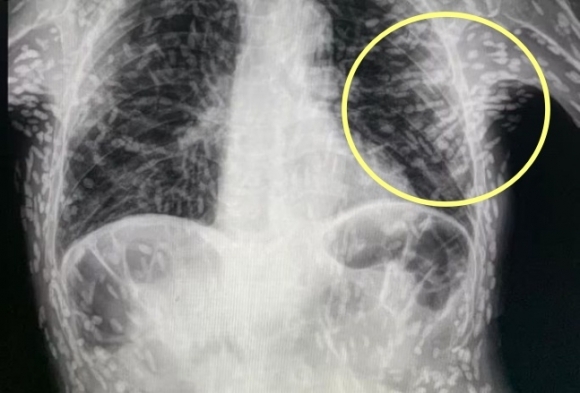

이 기생충들이 뇌조직으로 침투할 경우 생명에 위험을 초래할 수 있습니다. 회를 섭취한 남성의 사례에서도 복부통증과 피부가려움 등의 증상이 나타나, 엑스레이 결과 전신에 기생충이 퍼져 있는 것이 확인되었습니다. 따라서, 이러한 기생충에 감염될 경우 조기에 발견하고 치료하는 것이 매우 중요합니다.

마지막으로, 위에서 언급한 엑스레이 사진과 관련된 환자의 경우, 의료진은 해당 환자가 특별한 치료를 받지 않았다고 밝혔습니다. 만약 머리, 척수, 눈에 이상이 없다면 치료를 받을 필요가 없다고 말하고 있습니다. 또한, 사진 속의 유충들은 석회화되어 생존할 수 없는 상태이므로 특별한 조치가 필요하지 않다고 설명되었습니다. 그러나 해당 환자의 뇌에 낭종이 있는지 확인하기 위해 MRI 검사를 기다리고 있다고 전했습니다.